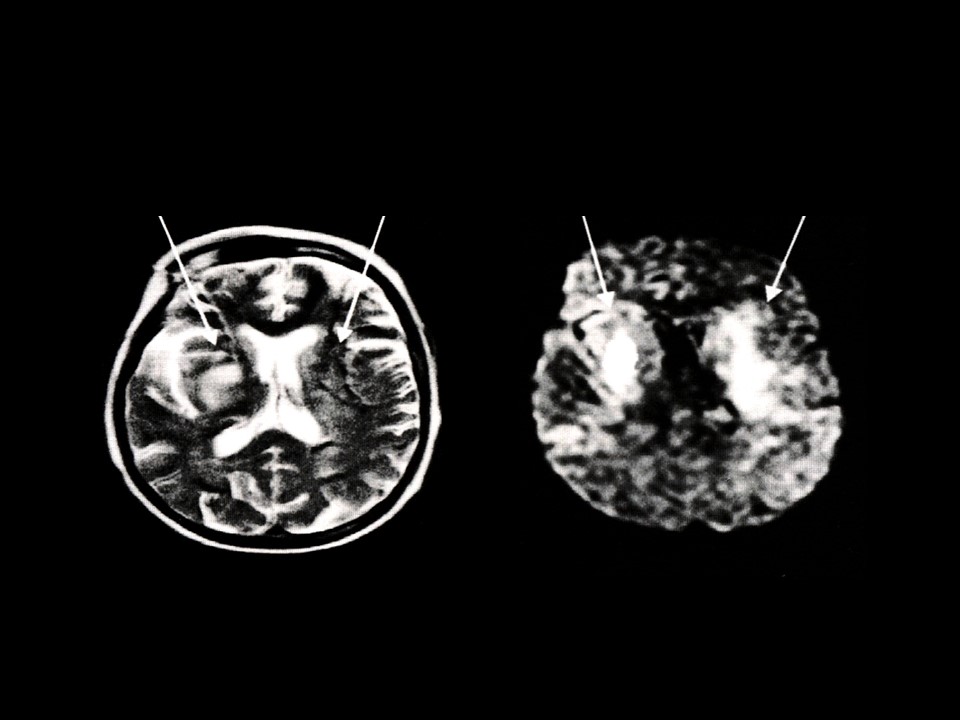

“超早期脑梗塞的CT和MRI诊断” 的相关文章